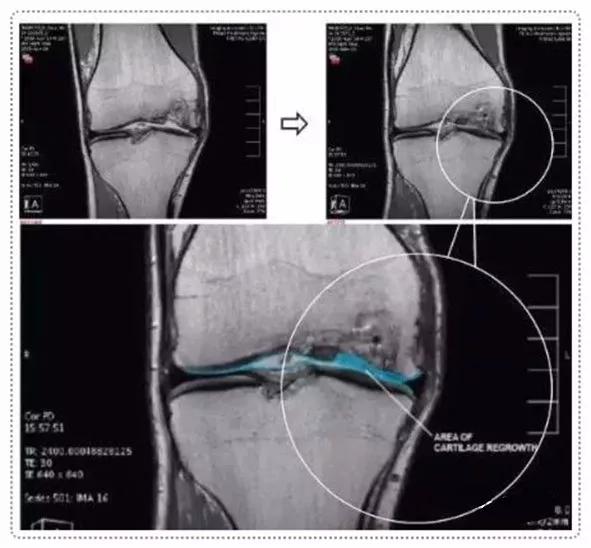

墨尔本干细胞治疗中心利用患者自身的间充质干细胞注入膝关节治疗膝关节损伤的临床研究是全球范围都较为知名的一项临床试验,这个试验共涉及70名患者,分为30名一组进行对照。最终结果显示,大部分参与试验的患者膝关节功能有了很大的改善:三分之二的患者膝盖疼痛程度和活动受限程度减少了一半,并且保持了一年以上。

2016年,曾在《干细胞转换医学杂志STEM CELLS TRANSLATIONAL MEDICINE》上报道过,在中外学者共同参与的一项研究中,用人自身来源的软骨细胞结合生物胶原支架,治疗软骨缺损,治疗后随访12个月全部患者的临床评分得到了提高,功能得到改善,疼痛得到缓解。

术后第二次关节镜检查(图a)。在所有4名患者中,移植区域具有保存完好的透明状软骨结构。4例活检标本的组织学检查结果表明,与邻近关节炎软骨相比,修复效果更好。组织显示存在软骨细胞样细胞,以及透明软骨样结构和基质。所有四个活检标本均为无异位钙化和血管化。并且没有发现炎症迹象。

上图a为治疗前关节镜检查结果,可以看出软骨存在缺损。图b为脂肪间充质干细胞联合PRP治疗,图c为治疗后结果,软骨得到了修复。